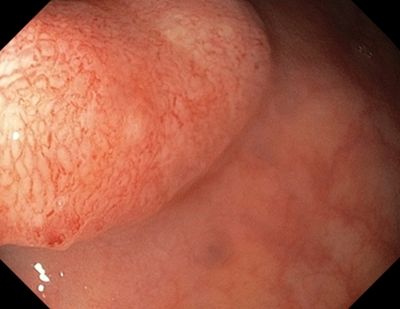

2 тип — характерний для аденоми

Колір: темніший (коричневіший), ніж навколишні

Судини: світліша ділянка в центрі, оточена більш товстими коричневими судинами

Поверхня: овальна, трубчаста, звивиста — наявність трубочок, лінійних або пучкових, світла ділянка в центрі, оточена коричневими судинами